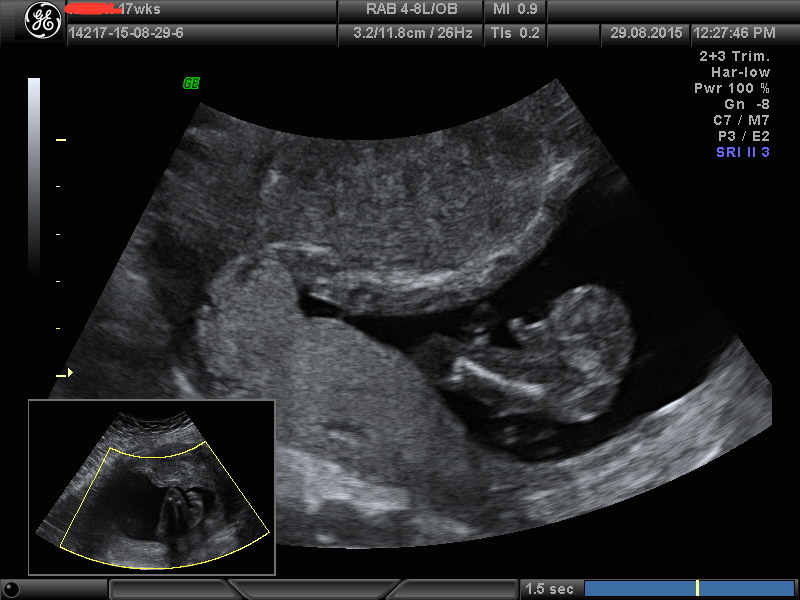

So is this a excellent boy shot or questionable ??